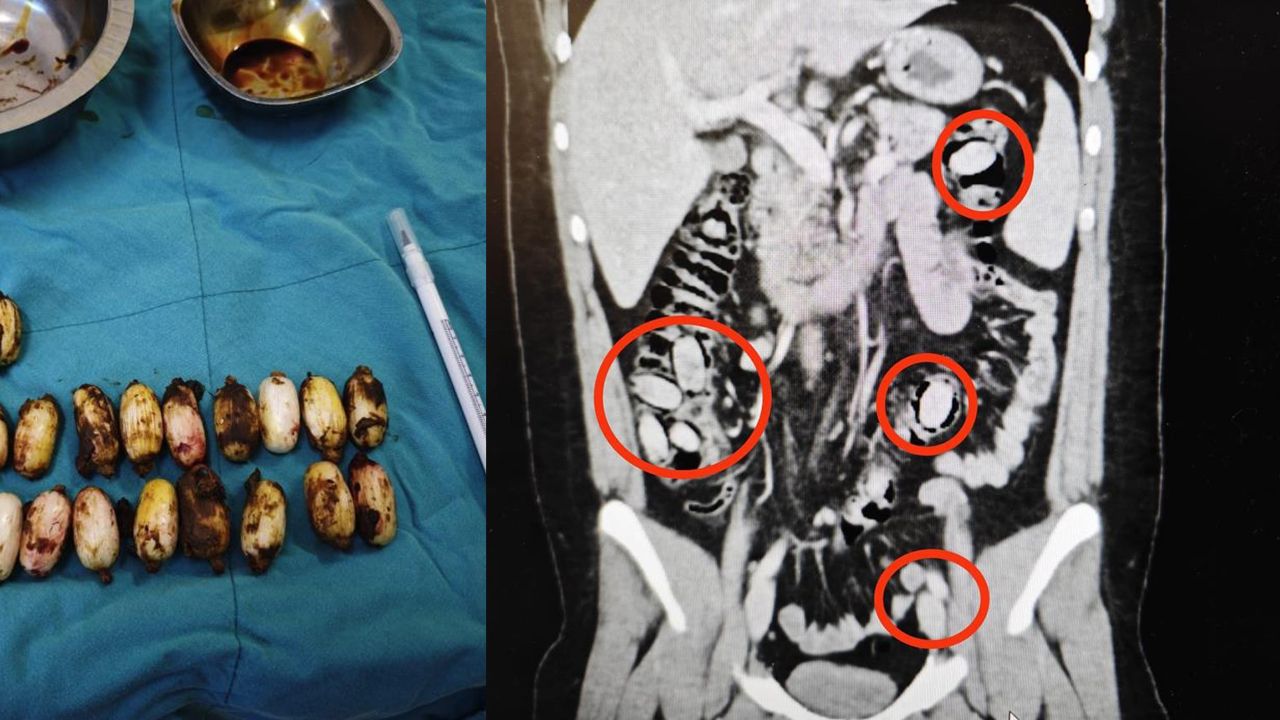

Yurtdışından Eskişehir'e gelen S.A. (25) isimli yabancı uyruklu şahsın kent girişindeki çevirme noktasında durumundan şüphelenilmesi üzerine hastanede yapılan detaylı tetkikler neticesinde yutmak suretiyle midesinde 44 kapsül metamfetamin maddesi taşıdığı anlaşıldı.

Cerrahi müdahaleyle söz konusu maddeler şahsın bedeninden çıkarıldı. Tedavisi akabinde şahıs tutuklandı. Yapılan titiz operasyon ile uyuşturucu maddelerin Eskişehir'de piyasaya sürülmeden ele geçirilmesi sağlandı.